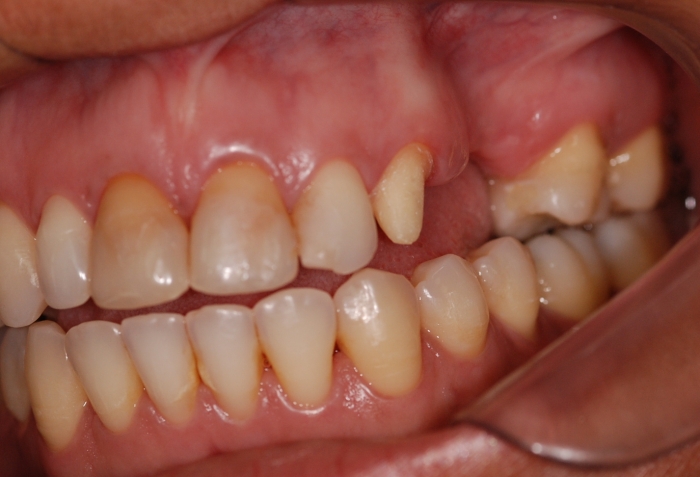

Imagens após o enxerto ósseo

Imagem e sorriso final do caso terminado em junho de 2011